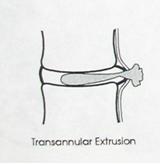

Экструзия (трансанулярная) с разрывом продольной связки: